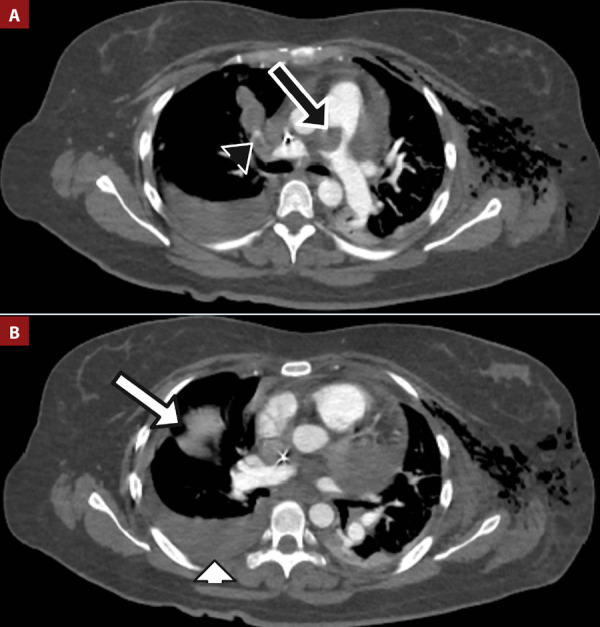

Systemic lupus erythematosus (SLE) is an inflammatory autoimmune disease with an important course due to systemic compromise. SLE is frequently associated with antiphospholipid syndrome, and pulmonary thromboembolism (PE) is particularly common. It is extremely rare for PE to be the initial clinical presentation and even more uncommon for it to coincide with cardiac tamponade, representing a challenge in diagnosis and management. We present a case of a 42-year-old woman with recurrent PE with severe pleural and pericardial effusion, hemodynamic instability, and cardiac tamponade. Laboratory workup revealed hypocomplementemia, leukopenia, negative SLE antibodies, and a positive lupus anticoagulant. This case emphasizes the importance of determining the etiology of PE, assessing risk classification, and implementing proper management, which are crucial for the patient's survival and outcome.